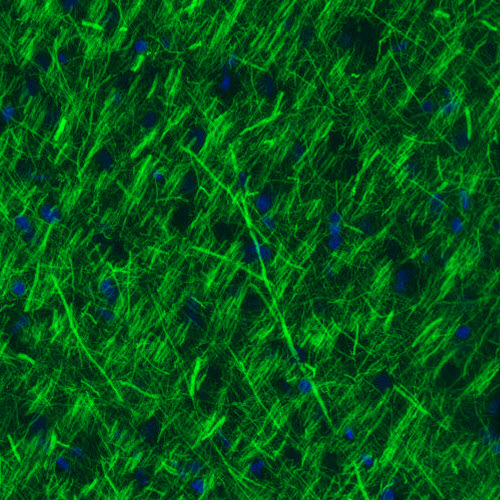

Immunohistochemical staining of rat cerebral cortex shows strong immunoreactivity in neuronal processes.